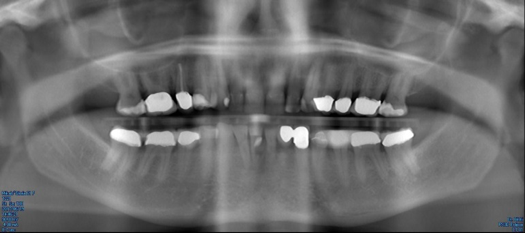

Every dentist has had to make a diagnosis based on the evidence presented during a patient's visit. Traditionally, a periapical radiograph was the line of choice. Changing from film x-rays to digital imaging with 3D cone beam computed tomography (CBCT) has enhanced the dentist's ability to more rapidly and efficiently diagnose (Figure 1). Now, the merging of digital photographs, intraoral scanning, and 3D CBCT data can be delivered to the dental laboratory electronically and ready for prosthetic and surgical treatment planning based on the patient-specific 3D data set taken in one visit at the dental practice. This complete 3D digital patient-specific record creates a hard and biomechanical foundation for accurate 3D planning.8

Fig 1. 3D CBCT imaging.

Figure 1